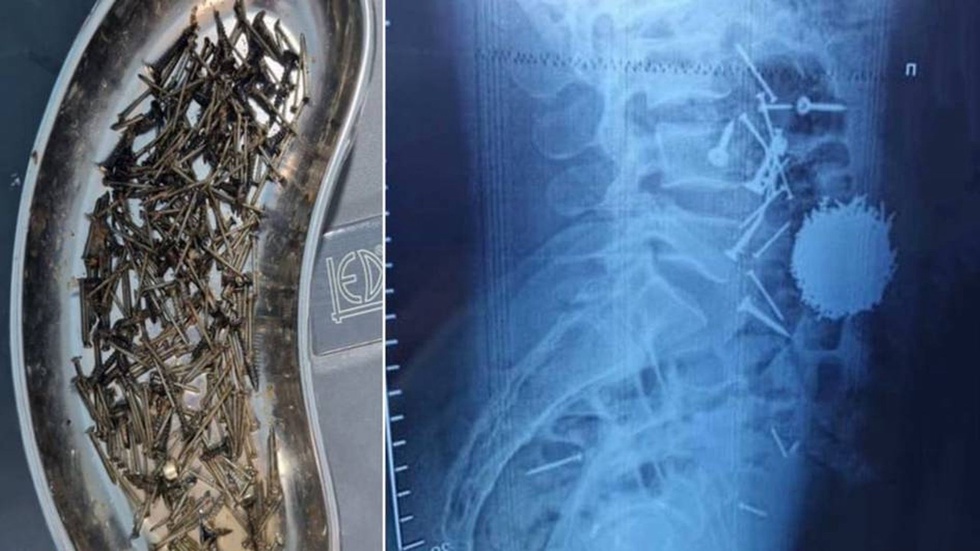

По результатам диагностики и лабораторных анализов, проведённых в отделении экстренного приёма, было выявлено, что в желудочно-кишечном тракте пациента находится большое количество металлических предметов, в частности гвозди и саморезы.

Как сообщил врач высшей категории Центра Йулдаш Кулиев, после завершения всех этапов подготовки пациента к операции была проведена хирургическая операция лапаротомия с гастростомией. Удалось извлечь из брюшной полости пациента большое количество, то есть около 200 граммов, металлических предметов.

Операция длилась около одного часа. В настоящее время состояние пациента хорошее, он свободно передвигается.

По имеющимся данным, мужчина находился в состоянии сильного стресса и, не контролируя свои действия, проглотил эти предметы, говорится в сообщении.